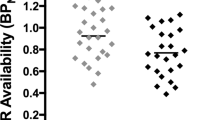

SMCT BPND was significantly different between groups in the AST (F=10.38, p=0.004), LST (F=4.95, df=1,23, p=0.036), SMST (F=4.33, df=1,23, p=0.049), and whole striatum (F=9.02, df=1,23, p=0.006), with HV having lower BPND as compared with CU in these regions but no difference in D3-rich regions (GP (F=2.12, df=1,23, p=0.159) and SN (F=0.89, df=1,23, p=0.354)) (Figure 1, Table 3). Similarly, voxelwise data comparing SMCT BPND parametric maps between HV and CU showed two clusters of significantly higher BPND in CU compared with HV at the level of the right caudate/GP and the left putamen (Figure 2). Percentage of displacement was not significantly different across groups in any brain region (Figure 1), except in the GP (F=4.39, df=1.23, p=0.049), with CU having less stress-induced changes (CU −5.03%) relative to controls (HV 6.15%). Voxelwise data confirmed the lack of difference between conditions. Interestingly, displacement in the LST was significantly different between CU (3.99%) and HV (−9.11%), when LST SMCT BPND was taken as a covariate. No other striatal region showed this effect. Years of cannabis use showed significant correlation with stress-induced [11C]-(+)-PHNO displacement in the LST (r=0.566, p=0.04; Figure 3) and a trend level correlation with [11C]-(+)-PHNO displacement in the entire striatum (r=0.522, p=0.067); however, these correlations are lost when age was added as a covariate. When SMCT BPND of the respective regions are taken as a covariate, the correlation with years of use in the LST remained significant (r=0.789, p=0.002). No correlation was observed between the PET-derived SMCT BPND, MIST BPND or percentage of displacement and PBI scores (maternal, paternal, or total subsets) or total lifetime cannabis use.

Left: Control task (SMCT) BPND in HV (filled circles) and CU (empty circles). Right: [11C]-(+)-PHNO displacement in response to the MIST between HV and CU. *p<0.05.